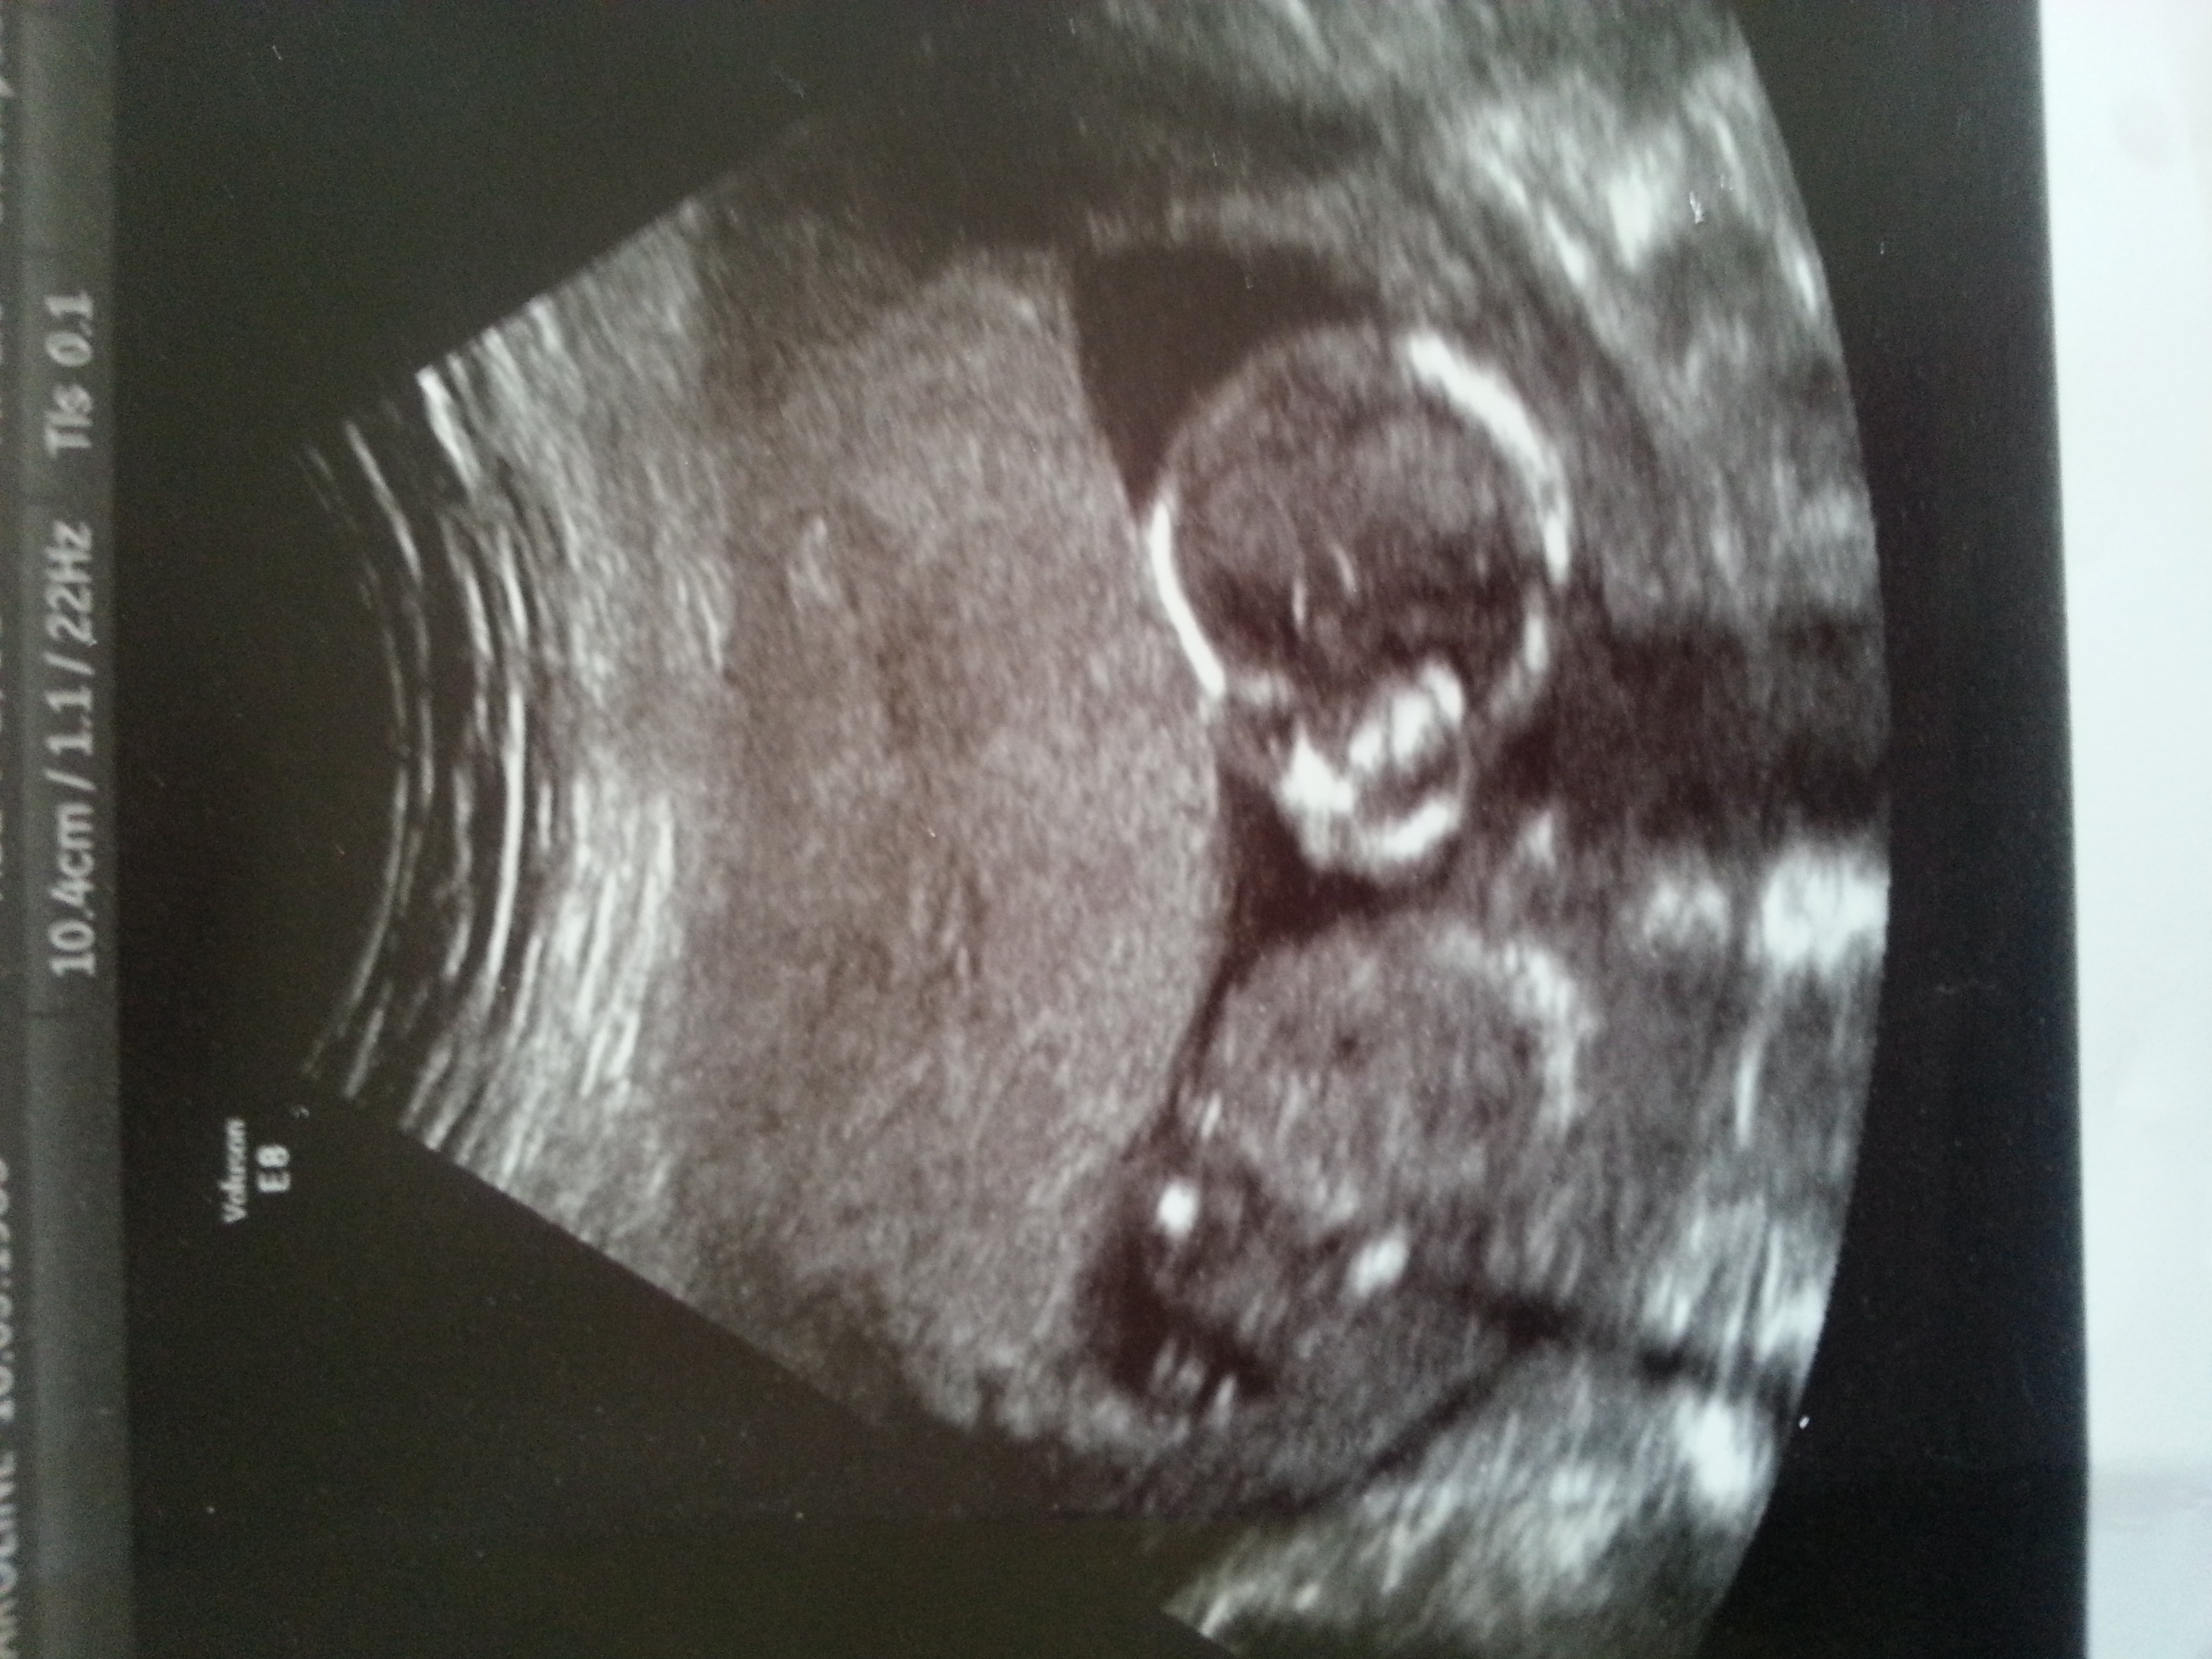

This is our 4th and last baby we have 3 children of the same sex my hubby getting the snip so deffo last 1, any guess would be appreciated as we don't:pregnant: find out for a month thanks caz... my scan pics are side on and front facing...Attachment 18768Attachment 18769